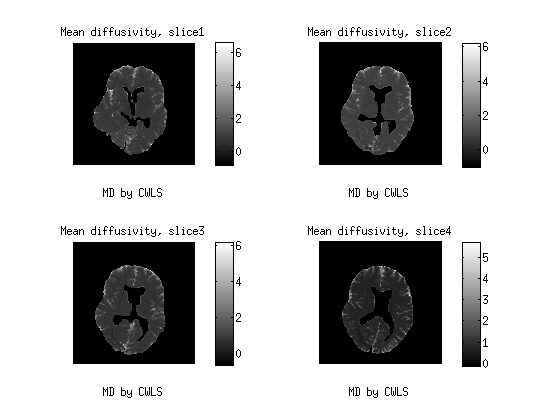

4.2 Real data

This data are part of a real experiment. It is consist of 2204 diffusion MR-images of the brain from an healthy human volunteer, taken from four -thick consecutive axial slices, and measured by a Philips Achieva Tesla MR-scanner. The image resolution is pixels of size . After masking out the skull and the ventricles, we remain with a region of interest (ROI) containing voxels. In the protocol, we used all the combinations of the gradient directions with the -values varying in the range 0, 62, 249, 560, 996, 1556, 2240 , with repetitions, for a total of 7 242 904 data points.

In this session, we depict the results by MD Fig. 3, FA Fig. 4 as well as MK Fig. 5 from the proposed CWLS and MLE methods.The diffusion weighted MR data is in the range of (0, 581), acquired by 32 distinct gradient directions with seven different b values. After comparison, we can see that the image constrasts by the MLE method gain much more detailed structural information, especially in Fig.4 and Fig. 5 than those by the CWLS in the same scales.

![[Uncaptioned image]](/html/1507.06780/assets/MD_cwls.jpg)

a

b